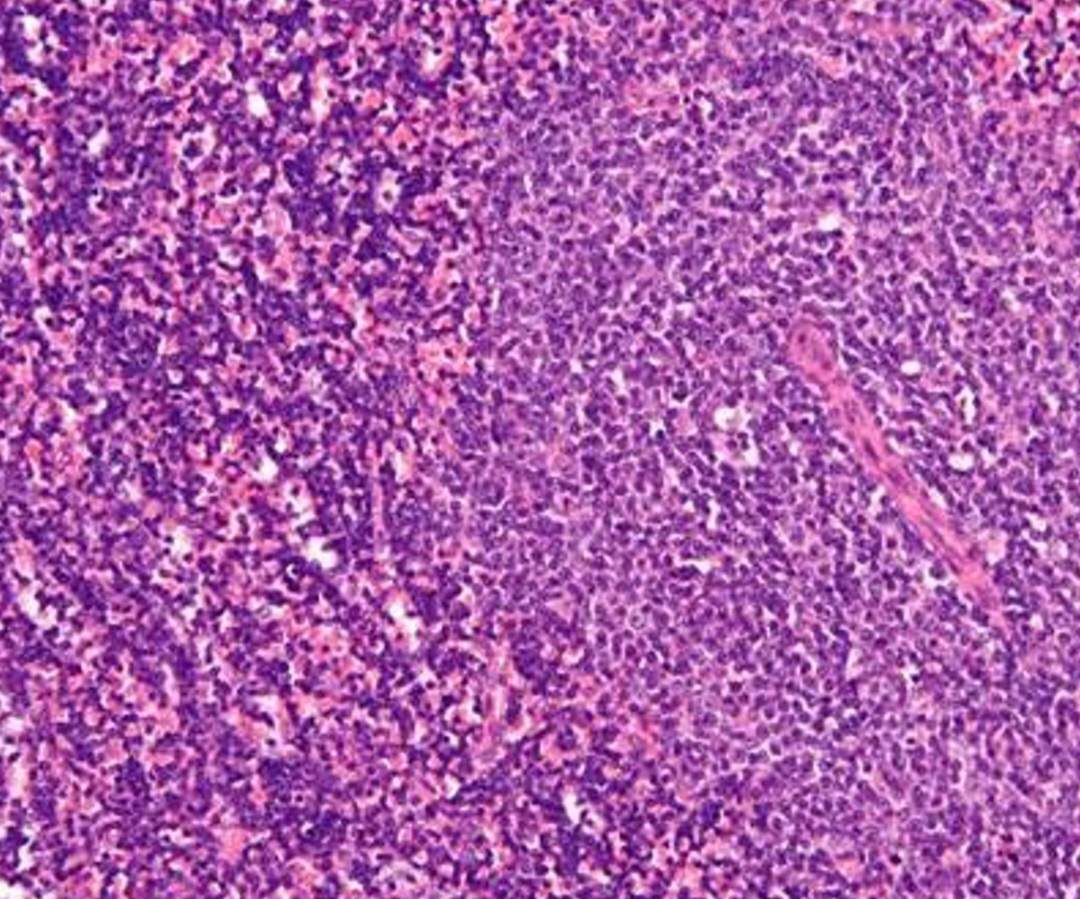

Leucemia linfocítica crónica

Los pasos iniciales del desarrollo de la leucemia linfoblástica aguda de células B (LLA-B) pasan desapercibidos en los niños. Varios estudios preclínicos han demostrado que la exposición a factores estresantes inmunológicos desencadena la transformación de las células B preleucémicas en una auténtica LLA-B, pero comprender cómo se lleva a cabo esta transformación es un desafío científico sin resolver.

El trabajo, publicado en 'Nature Communications', muestra en un modelo de ratón diseñado para investigar la leucemia linfoblástica aguda de células B, que el mal funcionamiento temporal de la señalización inmune innata juega un papel clave en este proceso e identifica cómo este mal funcionamiento está mediado por un mecanismo molecular que conduce a que el ratón afectado por este proceso acabe desarrollando leucemia linfoblástica aguda de células B. El ratón empleado en esta investigación se denomina Pax5+/- y el mecanismo molecular identificado está basado en la regulación negativa parcial de Myd88.